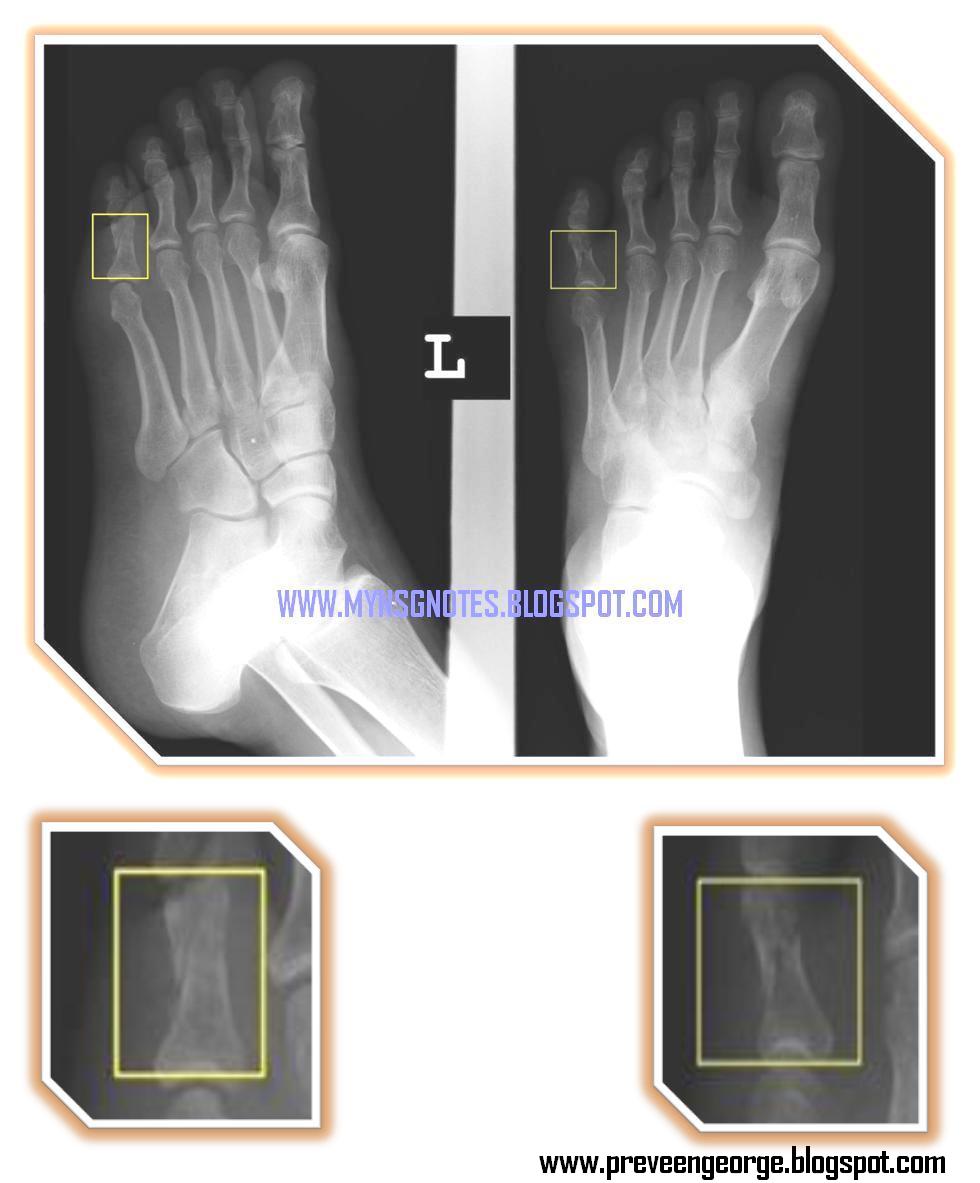

From mynsgnotes.blogspot.com

My Nurses Notes PROXIMAL PHALANX OF LITTLE TOE Buddy Tape Proximal Phalanx Fractures of the proximal phalanx of the big toe typically require fixation; Use one strip of tape to bind adjacent phalanges proximally. Phalanx fractures are common hand injuries that involve the proximal, middle or distal phalanx. Diagnosis can be confirmed with. Lateral middle phalanx fractures usually are ligamentous avulsion fractures; Buddy taping is a straightforward, effective, and convenient method for. Buddy Tape Proximal Phalanx.